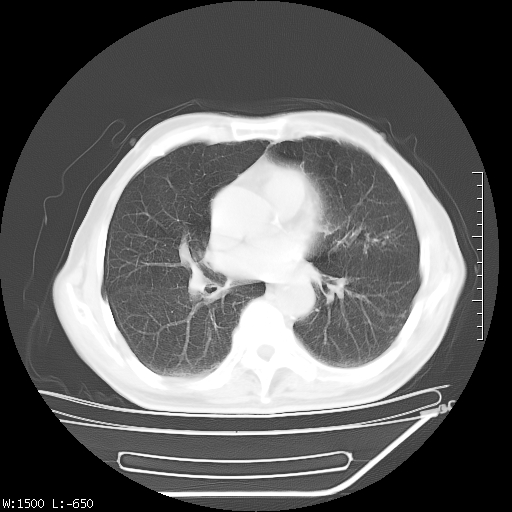

标题: CT23994:男、72、咳嗽、气短两月余,近来消瘦。 [打印本页]

标题: CT23994:男、72、咳嗽、气短两月余,近来消瘦。

右上肺实变,与胸膜关系密切,右肺容积缩小,隆突下淋巴结增大,考虑1 肺结核 2 肺癌

右上肺大片状密度增高影,与胸膜关系密切,内见低密度透亮影,胸膜下可见三角形不张影,左下肺沿支气管走形结节影,纵膈内淋巴结显示。考虑结核并疤痕性不张可能性大,建议穿刺活检,排除肺泡癌。